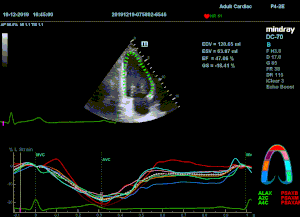

Всё изменилось с появлением технологии Speckle-tracking. Ультразвуковые приборы компании Mindray DC 8, 70, 80, Resona 6,7 оснащены данной функцией. Для использования необходим ЭКГ-канал. В чем же смысл данного технологического новшества? Прибор использует видео петли сечений миокарда, разбивает миокард на точки со стабильной визуализацией – speckle, и затем производит слежение каждой точки в течении нескольких сердечных циклов. Изменение пространства между точками дает нам представление о возможностях деформации миокарда, как продольной – Longitudinal Strain, так и деформации скручивания – торсии и Radial Strain.

На сегодняшний день в мировой клинической практике используется продольный Strain. Методика позволяет выявить нарушения в работе миокарда в каждом отдельном сегменте в среднем до 5 лет раньше клинического манифеста. Так же есть возможность оценки и диастолической функции, с гораздо более высокой чувствительностью чем тканевой допплер. Возможности радиального стрейна изучаются, за этой методикой будущее.

Как работать с данным методом? Для Longitudinal Strain необходимо записать видео петли апикальных сечений в память прибора: 4С, 3С, 2С. Для повышения качества трекинга рекомендуется производить запись на выдохе пациента. Затем произвести разметку по линии эпикарда, перикарда и центра миокарда. Нажатием кнопки «начать слежение» активируется программный алгоритм, видео петля оживает вместе с размеченными точками-speckle’ами. При необходимости производится коррекция. После анализа всех трех сечений можно получить данных продольной деформации как в среднем значении, так и по каждому сегменту миокарда левого желудочка. Нормальным показателем считается Longitudinal Strain -20%. Нижней границей -14%.

Видео примеры на приборе Mindray DC 70